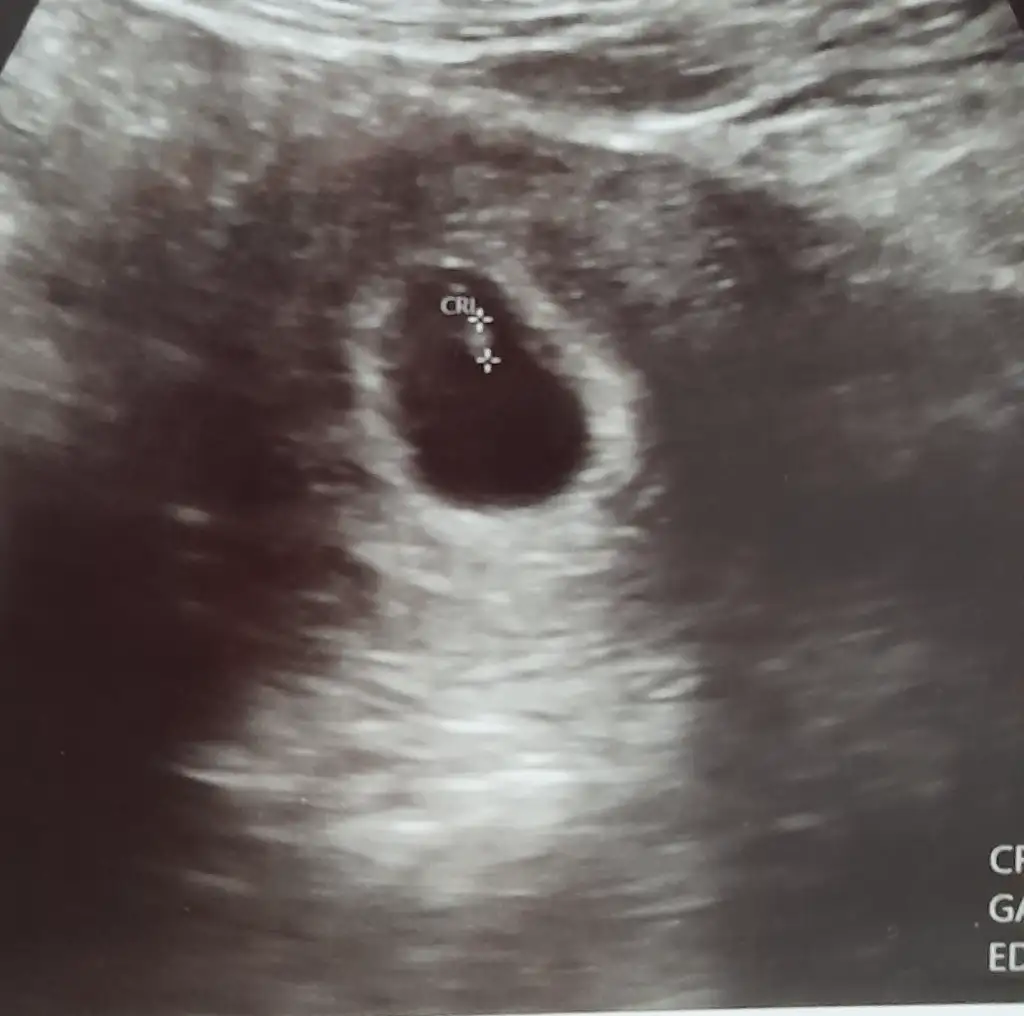

0 06Oznur06 Üye Kayıtlı Üye 10 Nisan 2025 166 42 13 28 12 Nisan 2025 Konu Sahibi Konu Sahibi Takitoki #942 6 haftalık vajinal ultrason görüntüsü, bize de bakabilir misiniz lütfen teyzeleri Eklentiler 1000138723.webp 15 KB · Görüntüleme: 42